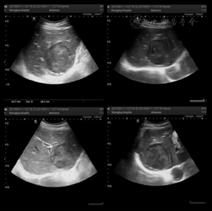

(1)病例特点:患者男性,69岁,以"消瘦厌食伴上腹胀3个月"于2013年1月9日收入我科,查体:未见明显阳性体征。既往史:无相关病史。实验室检查:肿瘤标志物AFP、CEA、CA19-9及其他生化检查未见明显异常。胃镜:十二指肠球部降交界移行处见隆起性病变,呈菜花样,表面充血、糜烂。超声胃镜提示:十二指肠隆起性病变(图7),活检病理回报:十二指肠黏膜慢性炎症。增强CT考虑恶性(图8)。(2)治疗:手术行胰十二指肠切除术。大体标本呈黄白色、鱼肉状、质硬肿物,边界模糊。(3)术后病理诊断为胰头炎症性肌纤维母细胞性肿瘤。(4)预后:术后电话随访4年余未见明显复发,恢复良好。